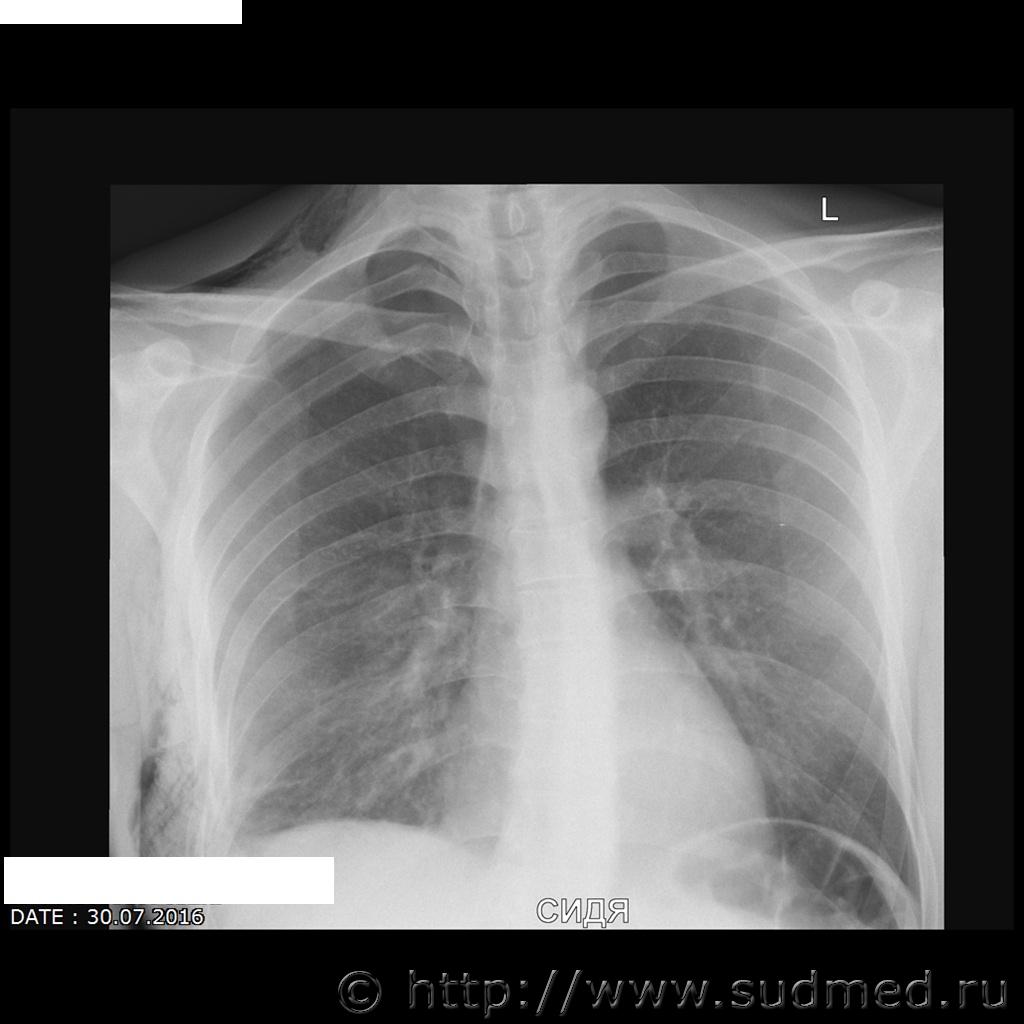

Травматический пневмоторакс справа, подкожная эмфизема, перелом (5, 7, 8 как минимум) правых ребер. Удары (удар) в правую боковую поверхность.

Согласен с коллегой: пневмоторакс справа (воздух в правой плевральной полости), обширная подкожная и межмышечная эмфизема правой половины груди (воздух в мягких тканях грудной стенки), вероятно, эмфизема распространяется и на шею. Переломы 5, 6, 7,8 ребер по передней подмышечной линии.

1. Представляется ли возможным объективно установить разрыв лёгкого по имеющимся рентгенологическим данным?

4. Возможно ли определить давность перелома ребер? Какой минимальный срок образования (по снимку от 30.07.2016 г.)

1. Пневмоторакс при тупой травме грудной клетки возникает вследствие разрыва легкого отломками ребер. Так что считайте разрыв объективно (пусть косвенно) установленным.

4. На сканах нет признаков регенерации. Минимальный срок - "только что".